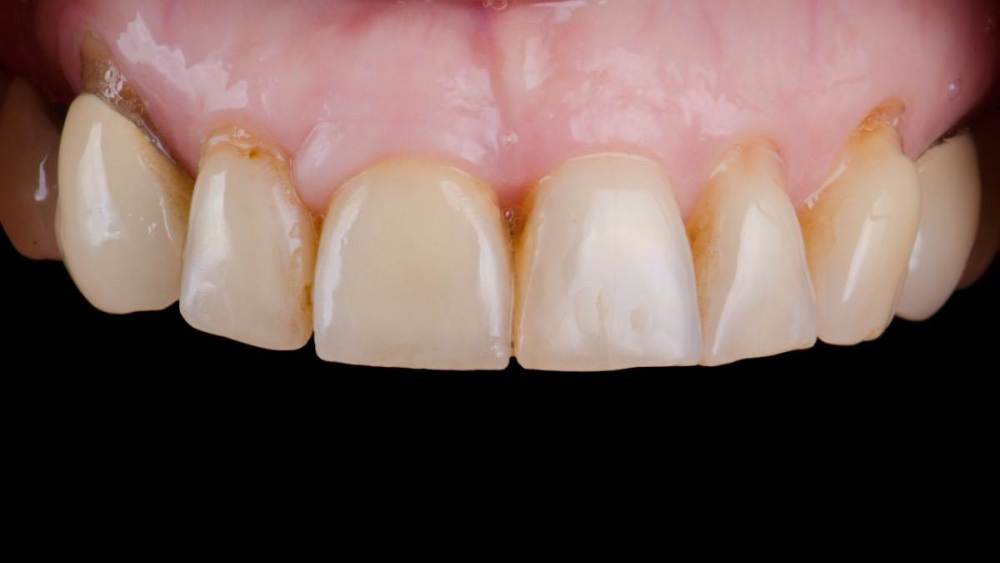

Владмир Опубликовано 20 марта, 2023 Автор Поделиться Опубликовано 20 марта, 2023 Здравствуйте коллеги. Работе 10 лет. Фото начальных этапов добавил 7 1 2 Ссылка на комментарий